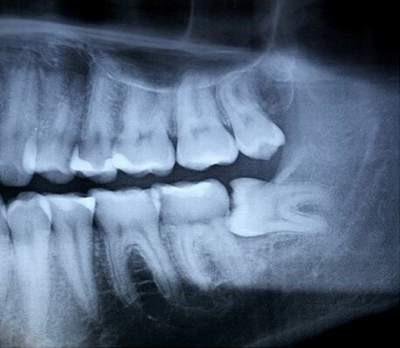

Nhổ răng khôn có đau lắm không luôn là nỗi băn khoăn của nhiều người, nhất là các đối tượng mới mọc răng khôn lần đầu. Vì răng khôn nằm ở vị trí cuối cùng trong cung hàm, liên kết nhiều dây thần kinh và có chân răng rất vững chắc. Vì vậy, quá trình nhổ răng khôn phức tạp hơn rất nhiều so với việc nhổ bỏ các răng còn lại. Nhưng với sự ứng dụng nhiều công nghệ hiện đại như hiện nay, nhổ răng khôn không còn là nỗi ám ảnh nữa.